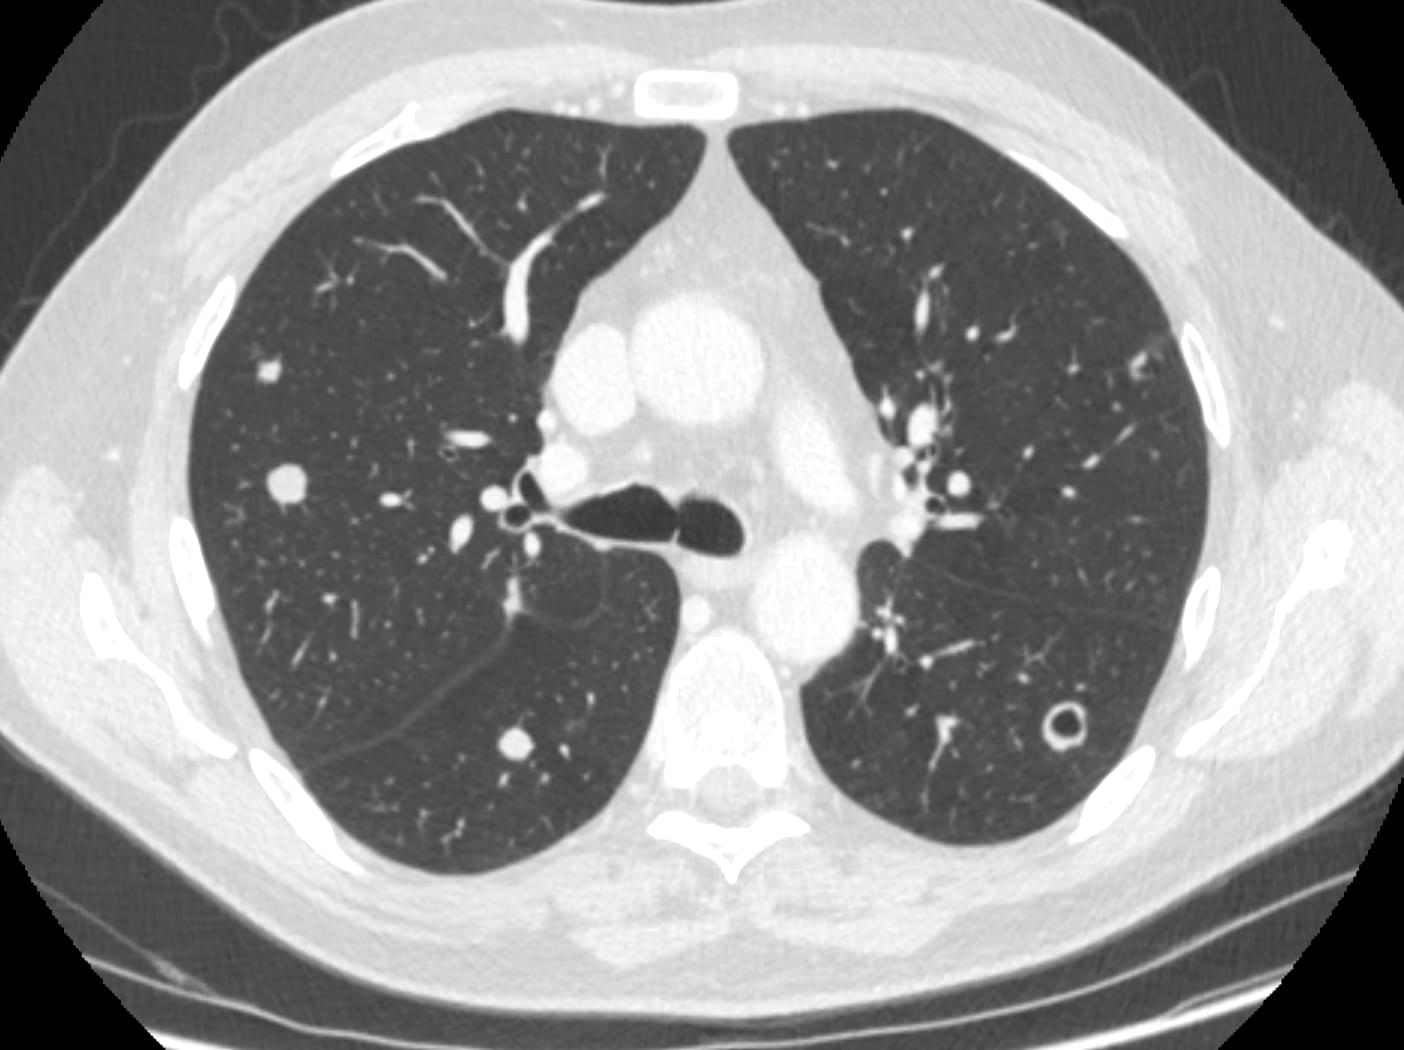

Here is an example of a cavitating lung metastases in a patient with colon cancer.

Metastases from which primary malignancy are known to cause pneumothorax?

Remember CAVITY for causes of Pulmonary Cavity

C – Cancer – MC: Squamous cell carcinoma

A – Autoimmune – Granulomatosis with polyangiitis / Rheumatoid arthritis

V- Vascular – Pulmonary emboli (blend or septic)

I – Infection – Bacterial or Fungal

T -Trauma – Pneumatocele

Y- Youth – CPAM/ Bronchogenic cyst / Pulmonary sequestration